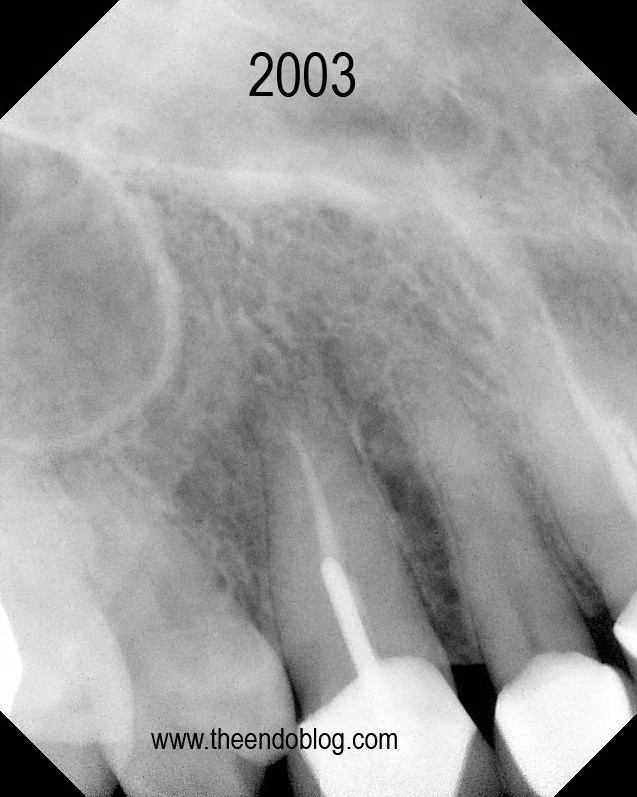

This patient has crowns on #6-#11.  Tooth #6 is causing a localized ache, affected by pressure and chewing. #6 is sensitive to percussion with normal probings. DX:  Prior RCT with Symptomatic Apical Periodontitis (SAP). The margins are suspicious, but apical surgery was chosen to address the infection without disturbing the existing crown.

Apicoectomy completed, no root fractures seen with microscope. MTA retrofill.